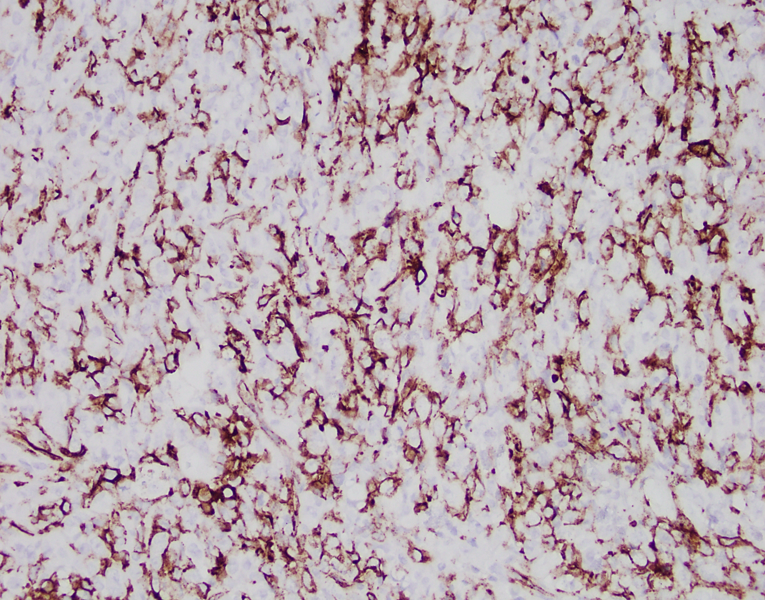

60 yr old male with a mandibular mass and lymphadenopathy. CBC showed marked absolute eosinophilia (60%; 6.06 x 10^3/cm). The mass is CD34+, CD45+, CD33+, patchy + for CD43, MPO. A) mandibular mass, B) submandibular lymph node, C) CD34, D) bone marrow bx

Sections of the mandibular mass and submandibular lymph node show markedly large, atypical cells with prominent nucleoli, with brisk mitotic activity. Eosinophils are prominent in the lymph node. The peripheral blood shows relative and absolute eosinophilia (60%; 6.06 x 10^3/cm), and the bone marrow biopsy showed eosinophilia with clusters of mast cells but no increase in myeloblasts.

Myeloid sarcomas have variable staining patterns, but markers typically positive are lysozyme, CD43, CD33, and MPO. CD34 can be positive (30-40% overall) in immature myeloid sarcomas. CD34 is strongly positive in this case, which is certainly helpful in distinguishing from other blastic or high-grade neoplasms like BPCDN.